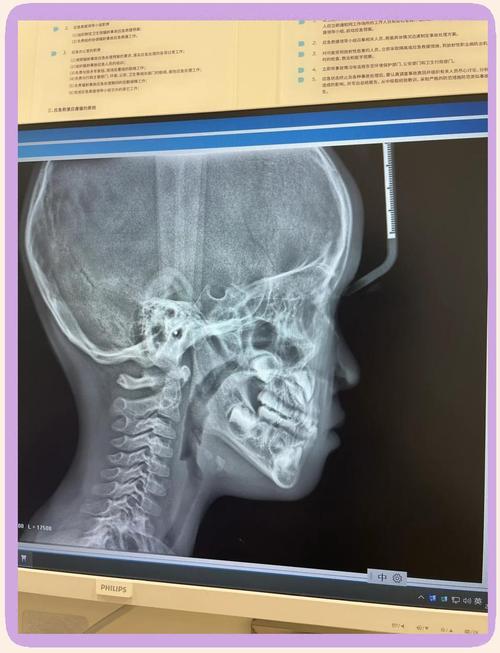

口腔正畸X光检查主要分为三类,各有其独特价值,曲面断层片(全景片)是最常用的基础检查,能一次性显示全口牙齿、牙槽骨、上下颌骨及部分颌面部结构,可观察是否有埋伏牙、多生牙、牙根吸收、牙槽骨骨密度异常等问题,辐射剂量低(约0.02mSv),相当于自然环境中2-3天的辐射量,适合常规筛查,头颅侧位片则是正畸诊断的“测量核心”,通过标记特定的解剖点(如蝶鞍、鼻根、上齿槽座点等),可定量分析上下颌骨的长度、宽度、高度比例,判断是否存在上颌前突、下颌后缩、面部不对称等问题,同时测量牙齿的倾斜角度、覆盖覆合程度,为矫治目标提供数据支持,CBCT(锥形束CT)则凭借三维成像优势,成为复杂病例的“精准导航”,能清晰显示牙根在颌骨内的位置、方向、形态,以及埋伏牙的萌出路径、骨量分布,适用于正颌手术前评估、种植体植入规划、疑难阻生牙拔除等场景,辐射剂量稍高(约0.1-0.3mSv),但单次检查仍在安全范围内,医生会严格掌握适应症。

| 头颅侧位片 | 测量骨骼发育、牙齿位置、覆盖覆合;分析上下颌骨关系 | 定量分析,指导方案设计 | 二维成像,无法显示三维结构 |